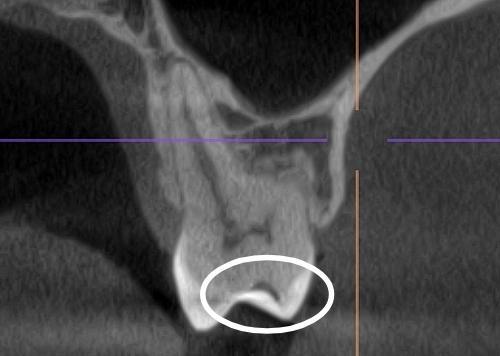

Недавно обращалась к терапевту с целью проверки состояния полости рта. На что получила ответ, что ряд жевательных зубов вызывают вопросы, одному даже нужна реставрация. До этого в течении полугода посещала 3ех терапевтов, приносила КТ, ответ один - никакого кариеса нет. По ощущениям пломба на одном из зубов имеет неровные границы, реагирует болью на сладкое. В этот раз сделала КТ с расшифровкой от известной сети независимых клиник. Отчета по зубам пока не получила, но КТ выдали сразу. Меня смущает несколько зубов. Может ли это быть кариес? 1(сверху) - 6 и 7 справа, 2/3 - 6ка слева, вид сбоку, вид спереди

Это скорее всего лечебные прокладки из не контрастных материалов...

Согласна с коллегой